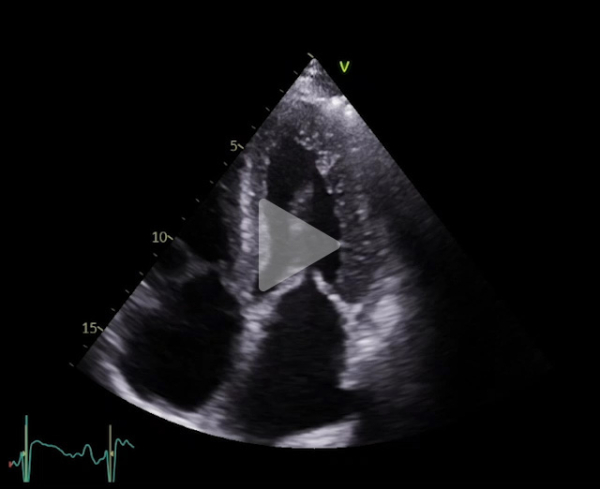

Vidéo 2

FEVG 40% en Simpson biplan, 45-50% visuellement. GLS -7%. Hypokinésie des bases et hyperkinésie de l'apex. VG non dilaté (DTDVG = 35mm, VTDVG =54ml/m2), hypertrophié (SIV = 18.5mm, PPVG = 19mm).

- DC = 3l/min, IC = 1.6l/min/m2 avec CCVG = 21mm et ITV sous Ao = 8cm

- OG dilatée à 40mL/m² (21cm2). OD dilatée à 19cm2

- Valve aortique tricommissurale, fine, pas de sténose ou fuite. Valve mitrale épaissie, pas sténose ou fuite

- Profil mitral restrictif, pressions de remplissage VG élevées (E/A =2.6, E/e’ moy = 22)

- Cavités droites non dilatées (Anneau tric =35mm)

- Fonction VD altérée (TAPSE = 7.7mm, S tric = 5.9cm/s)

- PAPS estimée sur IT modérée à 30 + 15mmHg (TAP 82ms)

- VCI dilatée ( 22mm), non compliante

- Lame péricardique minime